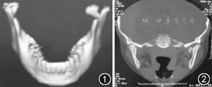

患者男性,11岁,2001年5月因"颏部碰伤1 h"就诊。专科检查:颞下颌关节区有压痛,前伸和侧向运动受阻,咬合错乱,前牙开

2 mm,张口度10 mm,开口型向左侧偏斜。CT检查:左侧髁突矢状劈开,髁头呈"分叉状",分为内外两部分,骨折的内侧游离端向前内旋转移位。右侧颏孔区纵行骨折,无移位(图1,图2)。